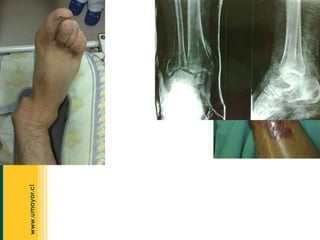

Lesión  infrecuente. Alta energía : acc. De transito Mediana energía : acc. Deportivos, caídas Luxación de Rodilla Debe lesionarse al menos 3 de las 4 estructuras ligamentosas de la rodilla. Lig. Cruzado anterior Lig. Cruzado posterior Lig. Colateral medial. Lig. Colateral lateral.

Examen vascular  de la extremidad. (10%-60% de lesión vascular en distintas series) Luxación de Rodilla La injuria vascular es prioridad ; debe repararse antes de 6-8h. (menor riesgo de necrosis y amputación). +/- 86% sobre las 8h.  Escasa circulación colateral de la arteria poplítea .

Clasificación : anterior, posterior, lateral, medial o rotatorias.  Luxación anterior (más frecuente):  por hiperextensión forzada. Lesión de la cápsula posterior, LCA y LCP. Asociada a lesión de la arteria poplitea. Luxación de Rodilla

Clasificación : anterior, posterior, lateral, medial o rotatorias.  Luxación de Rodilla Luxación posterior:  impacto frontal en la tibia. Lesión de LCA y LCP.  Rotatorias .  p/e:  posterolateral irreductible,  por combinación de fuerzas en varo y rotatorias con la rodilla en flexión.